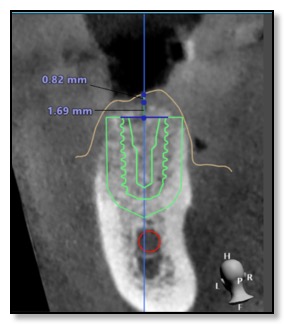

But thanks to recent advancements in digital dentistry, things have changed. Dr. Tsai is one of the few dentists in the Bay Area who has an in-house CT scanner (3D X-ray) and a 3D digital impressions camera.

She combines these technologies with a 3D printer. Here's how it works: she creates a digital model of your jawbone structure and overlays it with a 3D scan of your teeth and gums. Then, she aligns it with your natural bite to evaluate your biting and chewing patterns. This helps her determine the best position for the dental implant.

After this process, she collaborates with her lab to 3D print a template that acts as a guide for placing the implant with utmost precision regarding depth, angle, and location.

Designing this surgical guide is a meticulous process that usually takes about three weeks. It's especially crucial for all-ceramic dental implants, as well as standard ones.